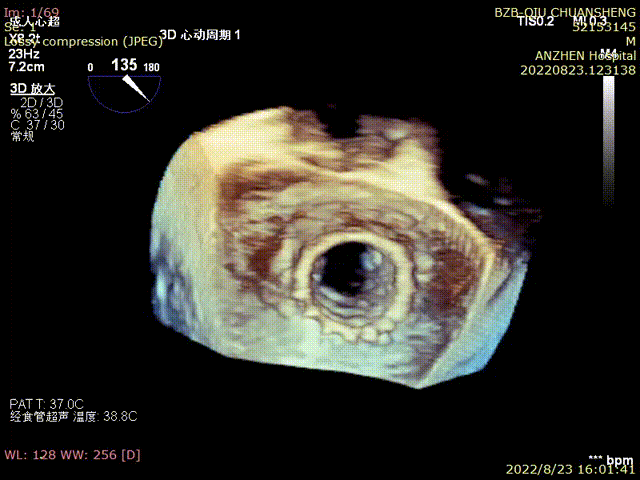

2.此次病例双生物瓣的瓣环均透视下不显影,即便造影模式也分辨不清楚瓣环,只能依靠三维超声引导下完成,术前的CTA扫描细节和结构特点预备方案,以及外科团队的经验尤为重要。

TEE-TMVIV-3D-撤出介入器